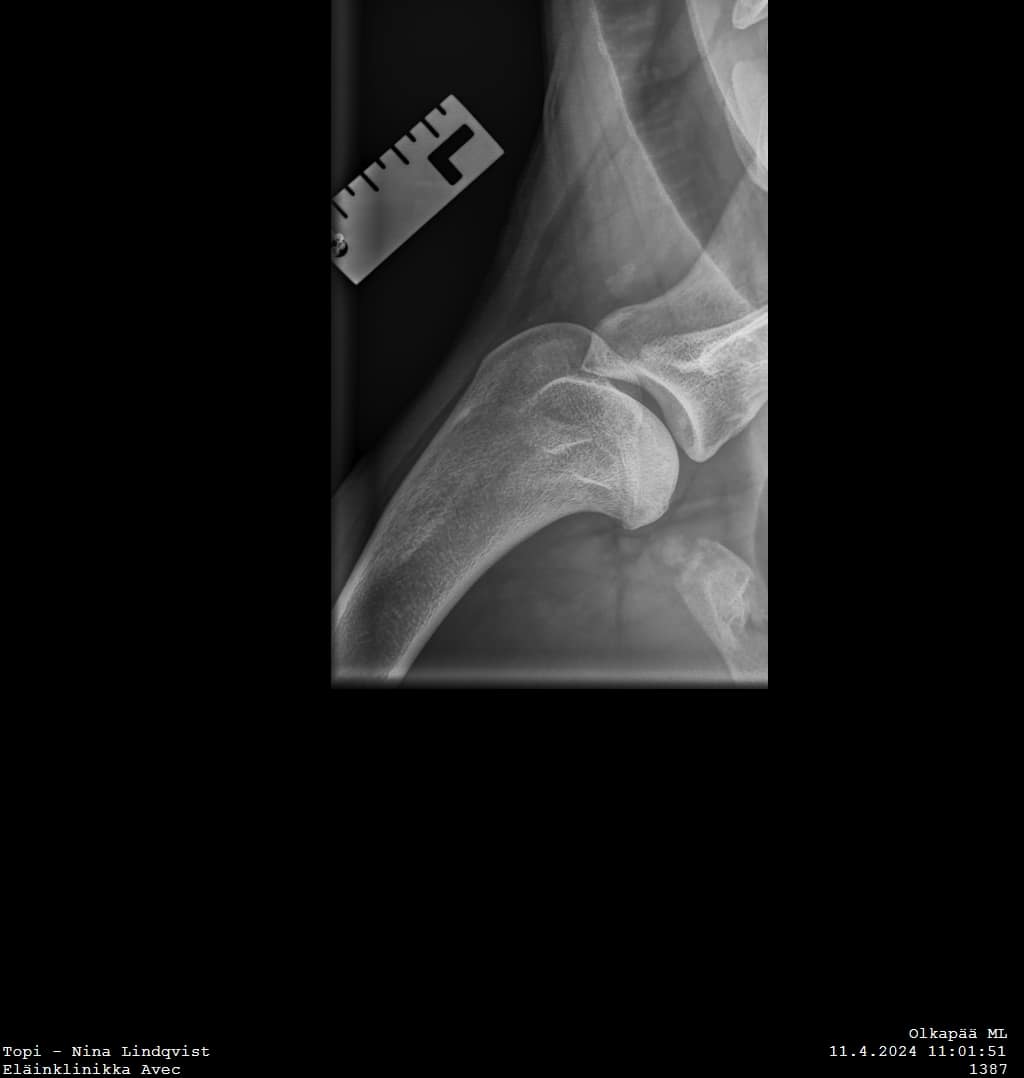

Topi was operated on Tuesday at Eläinklinikka Morelius by DVM Mikael Morelius. Both shoulders were operated by arthroscopy. On the left side there was a appr. 10 mm wide piece of cartilage removed. On the right side, which is also affected, the situation was calm and nothing was done. Everything went well!